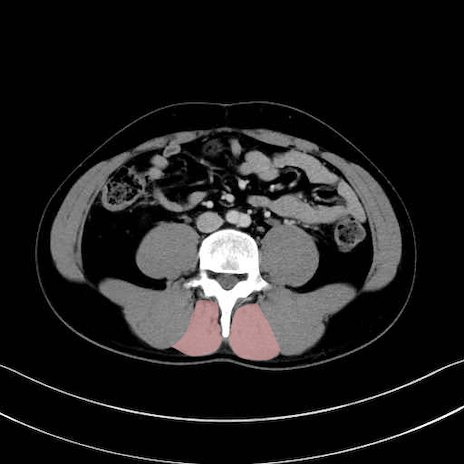

多裂筋 (Multifidus)